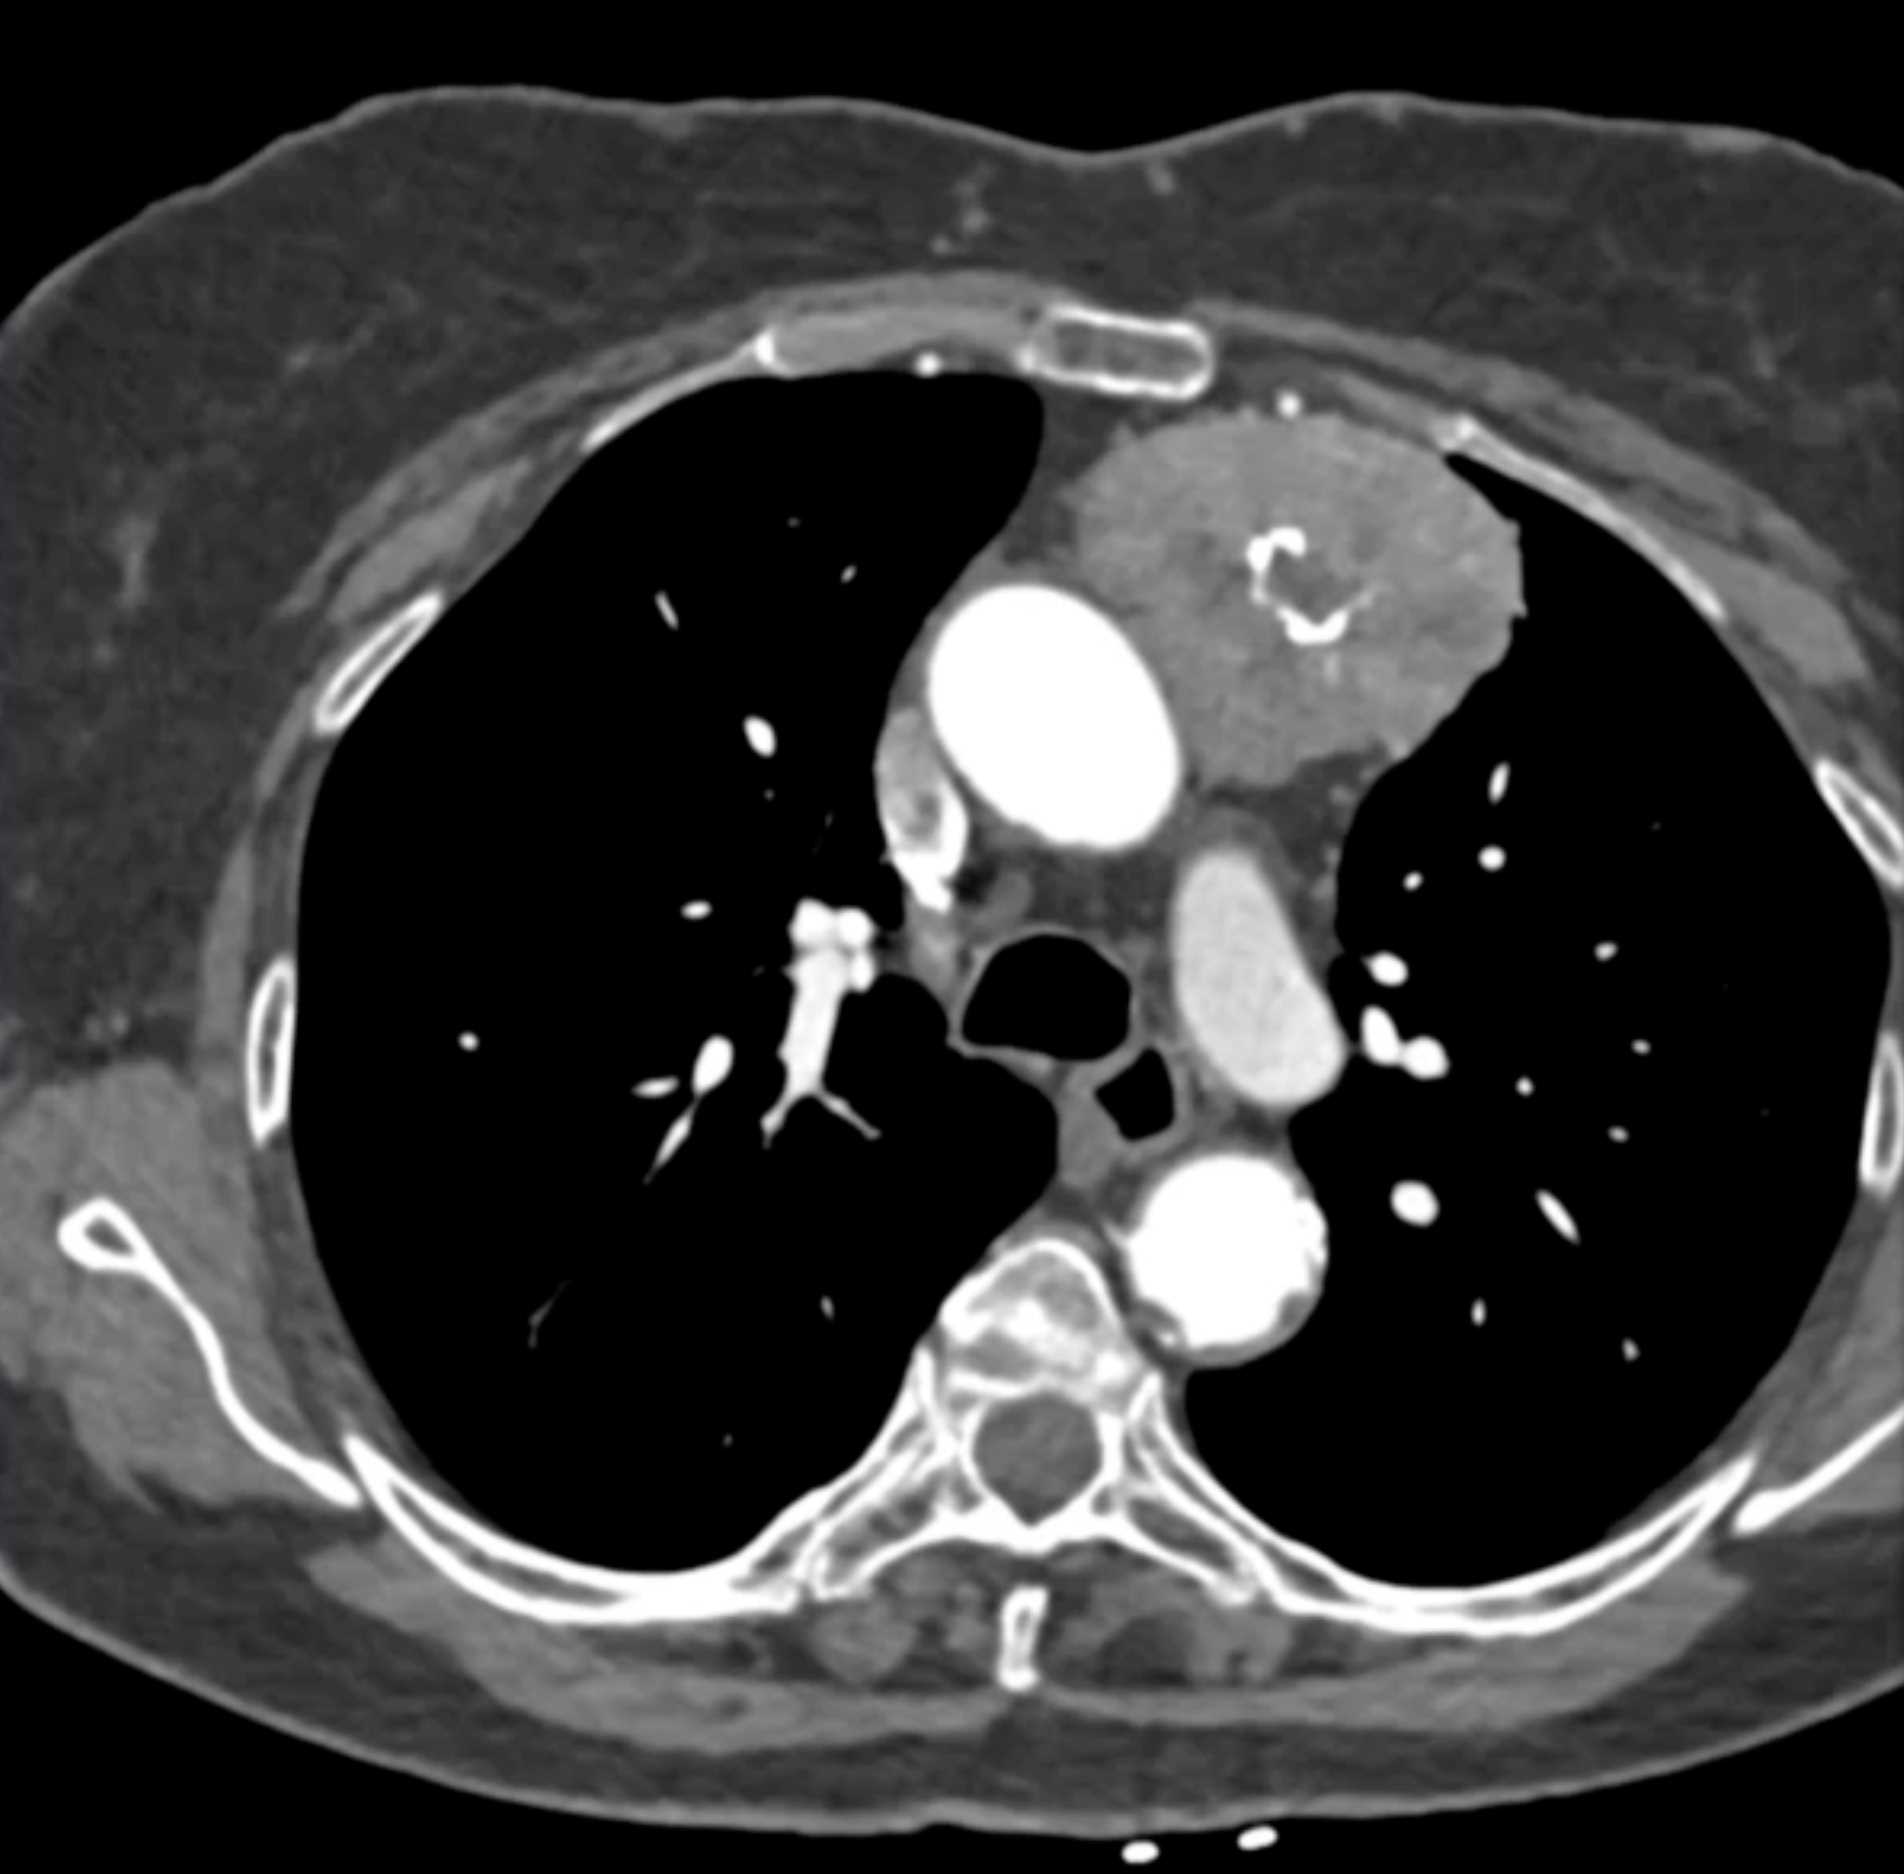

Thymic Carcinoma